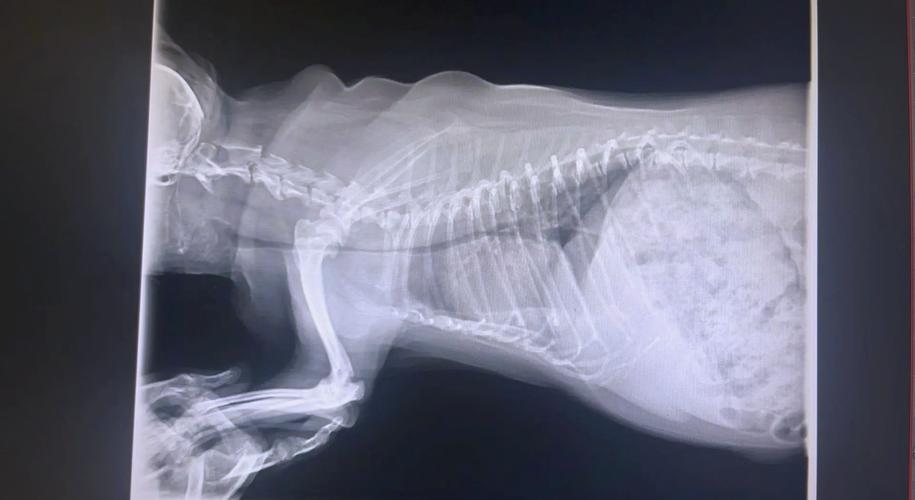

〖One〗、可以通过两种方法来诊断。胸腔X射线:拍摄时,又分为吸气及呼气两种方式。吸气:吸气时,比较容易诊断出颈部气管塌陷的问题。呼气:呼气时,比较容易诊断出胸腔内气管塌陷的问题。气管冲洗术:气管内视镜及细胞学检查可以进一步了解可能的病因。

〖Two〗、为了确诊狗狗是否患有气管狭窄,宠物医生会对狗狗进行一系列的检查。其中包括外观检查、听诊、X光、气管镜等,通过这些检查来全面了解狗狗的病情,确立最佳的治疗方案。狗狗气管狭窄一般需要使用药物治疗,或者进行支气管扩张手术和支气管支架置入手术等,需要根据病情的严重程度来采取最佳的治疗方法。